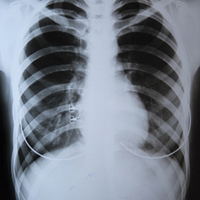

Необхідність переходу до комплексних, орієнтованих на пацієнта систем амбулаторної протитуберкульозної допомоги виникає у зв’язку з критичною ситуацією, що склалася в Україні та у всьому регіоні Східної Європи та Центральної Азії з розповсюдженням мультирезистентного туберкульозу (МРТБ). У нашій державі це перейшло у справжню катастрофу — ми входимо до п’ятірки країн світу з найтяжчим тягарем МРТБ! На жаль, Україна досі має і найгірші в Європі показники успішності лікування ТБ — виліковуються лише 71% нових випадків та 38,6% випадків МРТБ. За оціночними даними експертів ВООЗ, у 2015 р. близько 23% хворих на ТБ в Україні взагалі не було виявлено. Поширеність усіх форм активного ТБ у 2015 р. становила майже 85 осіб на кожні 100 тис. населення.

«Сьогодні у протитуберкульозних закладах України функціонує 16 тис. ліжок, але лише 55% таких закладів відповідають вимогам інфекційного контролю, що створює значний ризик інфікування стійкими штамами у стаціонарі, — інформувала директор Державної установи «Український центр контролю за соціально небезпечними хворобами МОЗ України Наталія Нізова. — Хворі на ТБ без бактеріовиділення можуть лікуватися в амбулаторних умовах без ризику інфікувати мікобактеріями оточуючих. Така практика довела свою ефективність у Європейських країнах та відповідає рекомендаціям ВООЗ».